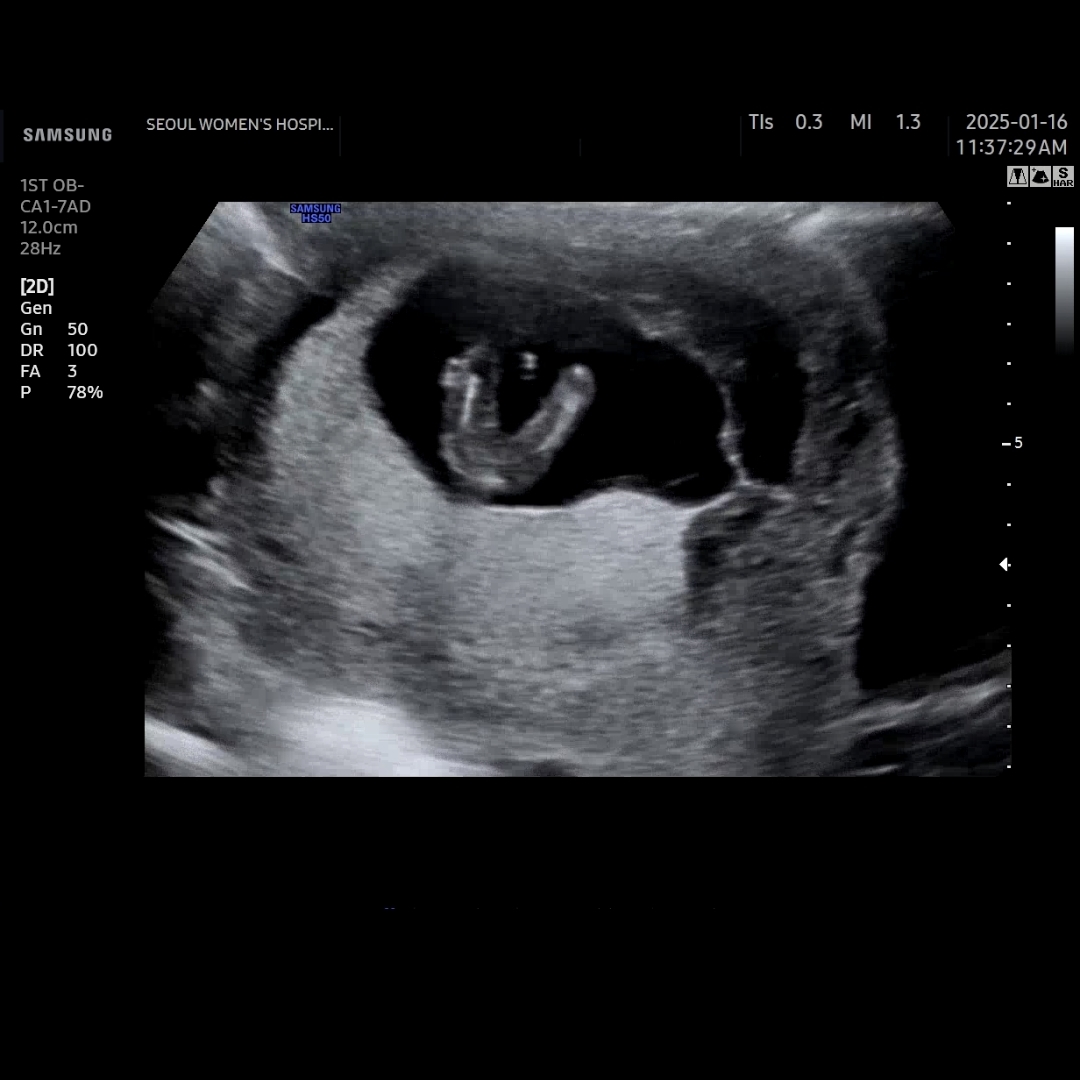

그럼 저의 딸래미, 찰떡이의 매끈한 하반신으로 마무리하겠습니다.